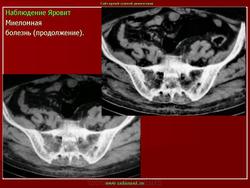

продолжение.

Миеломная болезнь